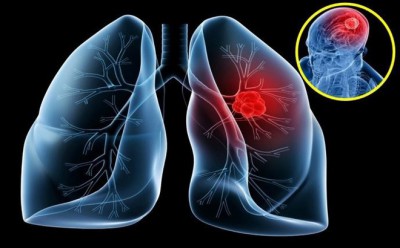

Khuyến nghị về chăm sóc sau khi điều trị ung thư phổi

Sau quá trình điều trị ung thư phổi người bệnh thường rơi vào trạng thái mệt mỏi, kiệt sức và đôi khi lo lắng cho chính tình trạng sức khỏe của mình. Điều này vô tình sẽ...

Khối u Carcinoid phổi có gì khác so với ung thư phổi thông thường

Các khối u carcinoid phổi là một loại ung thư phổi hiếm gặp. Chỉ 1% đến 2% ung thư phổi là khối u carcinoid và thường phát triển chậm. Đây là một loại khối u nội tiết thần kinh, có nghĩa là...